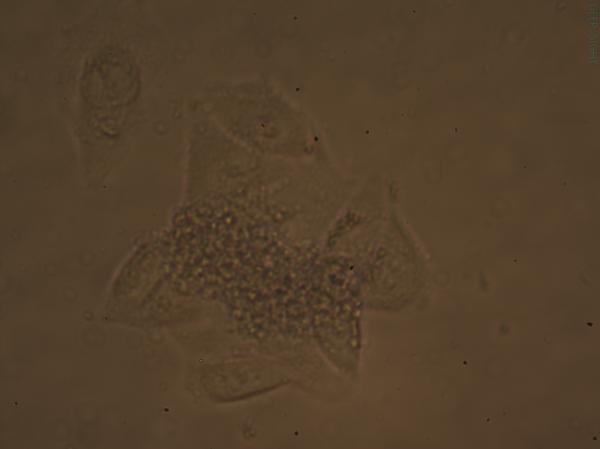

Hela细胞培养问题求助 已有1人参与